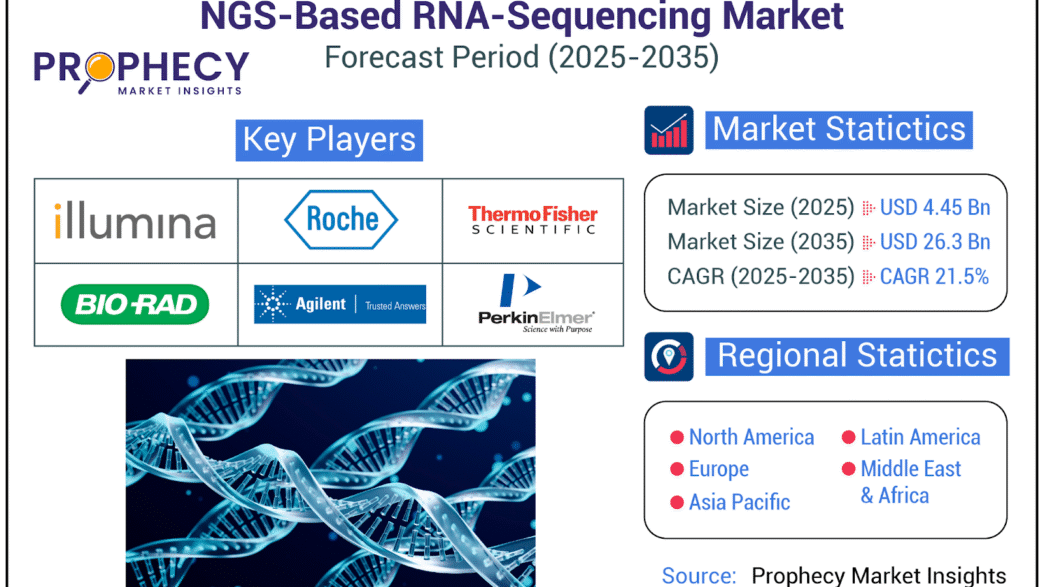

Discover AllNGS-Based RNA-Sequencing Market Intelligence Report: Recession Readiness and Tariff Implications

The NGS-based RNA-sequencing market is set for robust growth through 2035, driven by biotech advances, research demand, and precision medicine expansion.